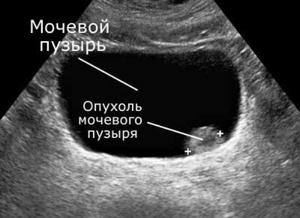

Диагностируют ультразвуком также пониженное давление или гипертрофию в простате у мужчин, наличие камней, повреждение мочеиспускательного канала, мочеточников, воспаление в простате, острые или хронические очаги воспаления на слизистой, хроническое поражение чашечно-лоханочной системы почек, опухолевые процессы в мочевом пузыре и близко расположенных органах, кисты.

Неподвижные эхогенные участки на стенке пузыря могут являться приросшими к слизистой оболочке конкрементами, доброкачественными аномальными разрастаниями тканей, называемыми полипами, врожденным дефектом, заключающимся в сужении мочеточникового устья и формировании округлого выпячивания внутри мочеточника.